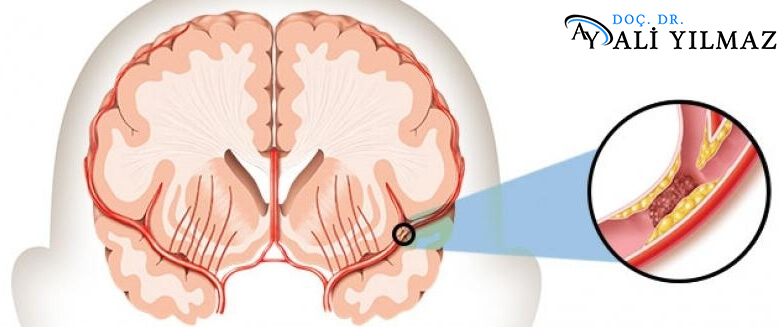

İnme-Karotis Arter Darlığı

İnme, kalıcı sakatlık ve ölümün önemli nedenlerinden biridir. İnmelerin çoğu iskemik nedenlere bağlı olup, bu hastaların yaklaşık üçte bir...

Endovasküler İnme Tedavisi

İnme endovasküler tedavisi, kan pıhtılarının beyin damarlarını tıkaması nedeniyle ortaya çıkan ani beyin fonksiyon kaybını önlemek için cerrahi olmayan bir t...